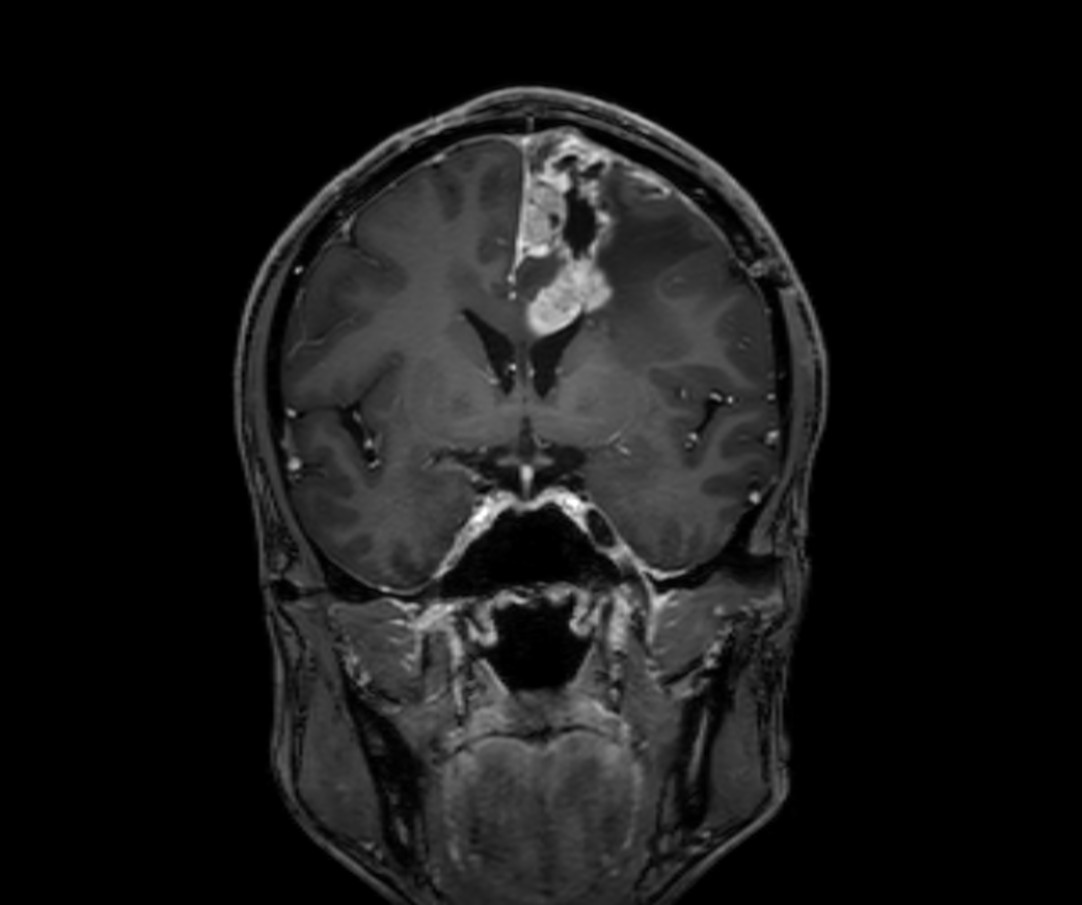

SmartSpeed Precise imaging for brain with glioblastoma

Kyushu University Hospital Japan